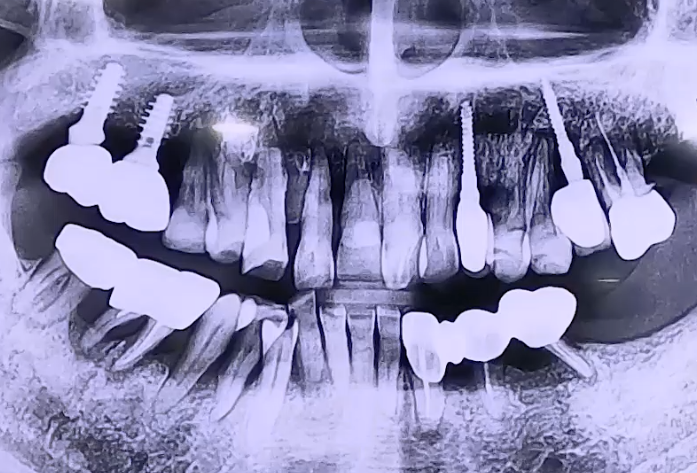

AFTER

따라서 기존 임플란트 중 문제가 되는 것들도 함께 보다 굵고 튼튼한 임플란트를

사용하여 전반적으로 복원해 드리는 치료를 진행하였습니다.